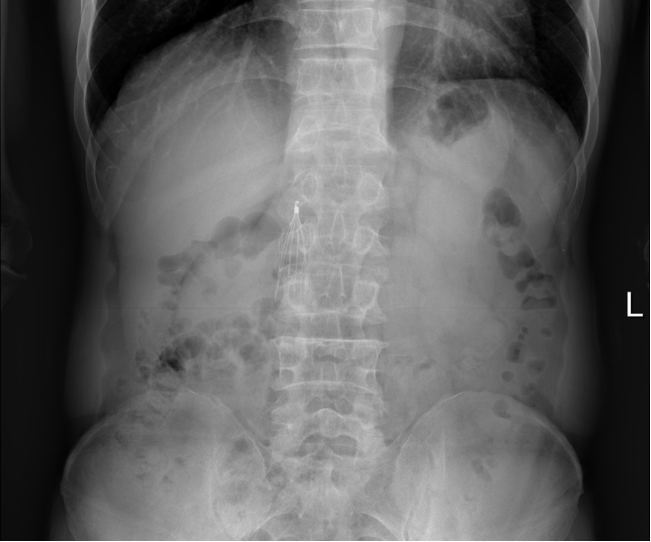

图为:入院立位腹部平片